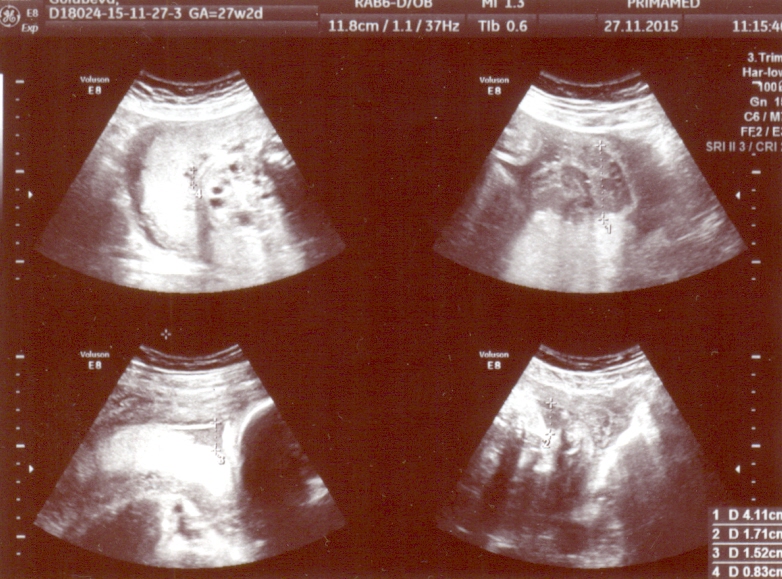

Спасибо доктор, немного утешили!Все станет ясно завтра-консилиум.И я так понимаю,что поликистоз все-таки,если можно так сказать лучше чем мультикистоз.А так почки увеличены правая-64*40,а левая-67*34,паренхима с множественными мелкокалиберными кистами.БПР 73мм,ЛЗР-96мм,ОГ-268мм,ОЖ-249мм ДБ-49мм.

Михаил Юдович,прикрепляю снимки.Заранее благодарна!Вы дали нам надежду и может сегодня ночью я посплю.Да кстати мне 39 лет и это мои 2 роды,первому ребенку 16 лет и никаких проблем с почками у него нет.Хотя у меня до 1-й беременности один раз были проблемы -в 1998году и что-то там было( 1 почка увеличена и раздвоена).Но после этого ни разу за 16 лет я про почки не вспоминала,еще у меня резус отрицательный у мужа положительный.Может какие-то из этих признаков повлияли на эту патологию?

3olg76uyar, Выскажу своё мнение, которое не является окончательным заключением, т.к. УЗИ надо видеть "в живую" Я думаю, это не мультикистоз, а другое, также очень тяжёлое заболевание. Это больше похоже на неонатальный тип поликистоза почек. Почки очень большие. Я смог разглядеть надпись - они по 6 см в длину. Это размер почек годовалого ребёнка. Паренхима в почках есть (что исключает мультикистоз), но она очень гиперэхогенная и высока вероятность продвинутой почечной недостаточности с рождения. Столь большие почки снизу давят на лёгкие и могут вызвать их недоразвитие. Подобный тип поликистоза почти всегда сопровождается фиброзом печени, который может быть пока не виден по УЗИ, но прогрессирует в течение нескольких лет после рождения.

Здравствуйте!Сегодня был консилиум и диагноз мультикистозная дисплазия обеих почек подтвердился.Правая почка-61*35,левая-65-32,ткань перенхимы почек представлена множеством анехогенных включений Д до 13мм. Мочевой пузырь 20*15.ИАЖ-8 см.Беременность 28 недель.При этом все остальные органы в норме без потологий.Следующий консилиум через 3 недели и я так понимаю шансов практически нет.